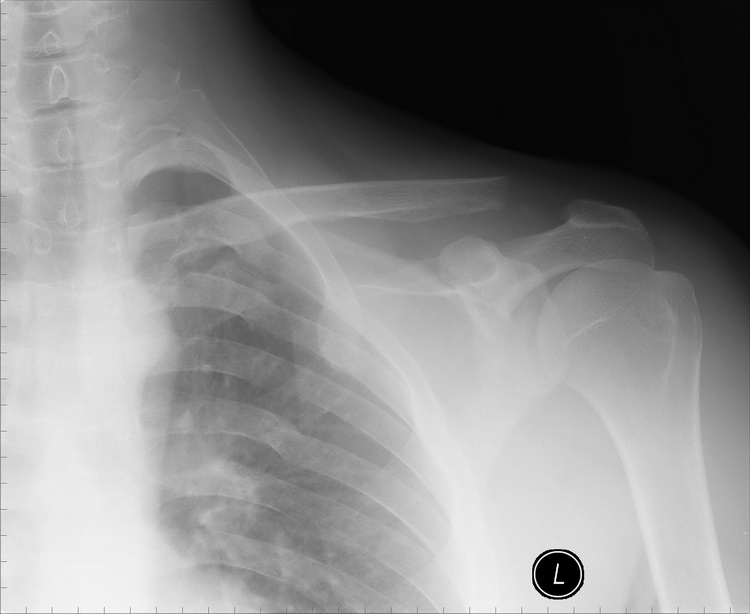

Re: Остеолиз ключицы

Еще снимки.